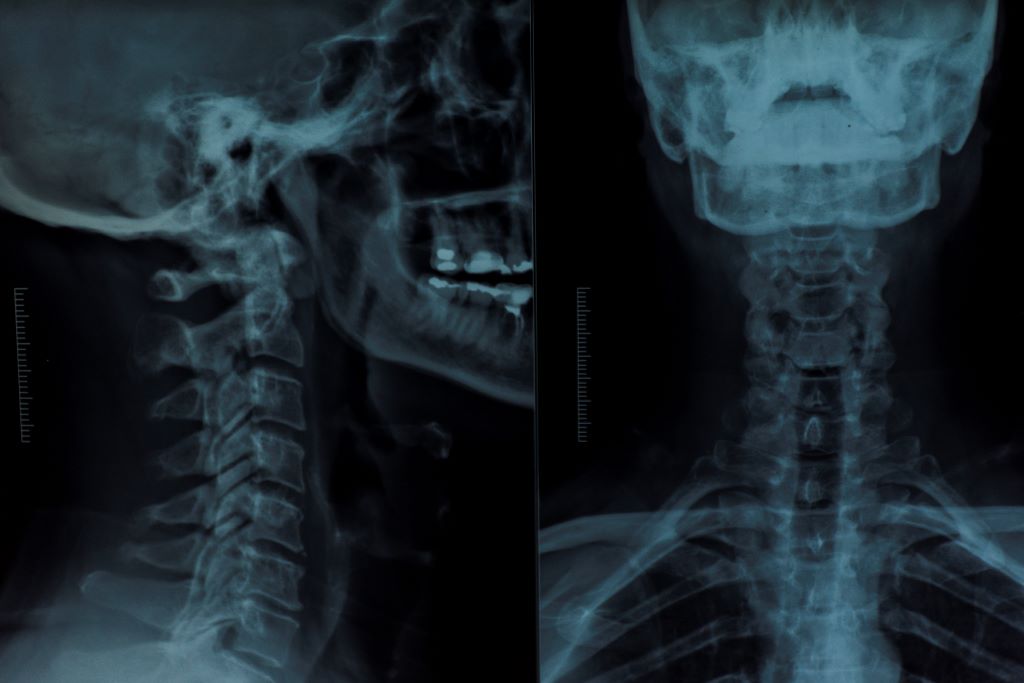

X-Ray

X-rays are a type of radiation called electromagnetic waves that create pictures of the internal body. X-rays are commonly used to diagnose fractures in bones but can also be used to diagnose pneumonia or monitor joint issues. The duration of the scan varies by body part and x-rays can be performed standing or lying down.